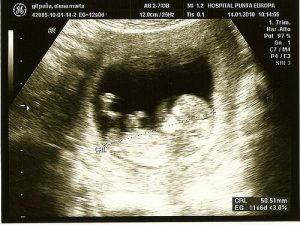

超音波検査

超音波による検査は、ごく一般的な検査の一つです。問題の検出に加えて、生まれる前の赤ちゃんを画像として表示することができます。

これにより、赤ちゃんの性別を知ることができますし、また、心不全や染色体変化などの早期異常の検出も可能です。

第2レベルの超音波検査は、胎児に生じる可能性のある欠陥を観察するために推奨されている検査です。スクリーニング検査で異常の可能性がある場合は、第2レベルの超音波検査が推奨されています。

音波を用いて画像を生成する装置を介して行われる安全な検査なので、音波によって赤ちゃんを傷つけることはなく、子宮内を観察することができます。